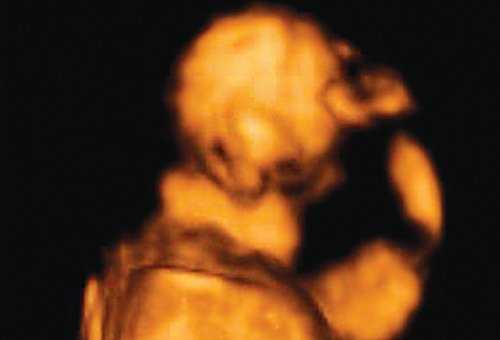

Революцией в пренатальной ультразвуковой диагностике явилось появление объемной эхографии, которая, обладая такими качествами, как неинвазивность, безопасность и возможность многократного применения у одной пациентки, имеет высокую информативность в исследовании анатомии плода и изучении его фенотипа. При применении различных режимов объемной эхографии абсолютно очевидно их преимущество по сравнению с обычным сканированием. Детально можно изучить лицо плода (рис. 1-4) в различные сроки беременности, начиная со сроков первого пренатального скрининга в 11-14 нед, конечности плода, причем не только их наличие и положение (рис. 5, 6), но и состояние и количество пальцев (рис. 7-9) как на руках, так и на ногах. Также можно изучить позвонки плода (рис. 10), состояние твердого нёба (рис. 11, 12), строение наружного уха (ушной раковины) (рис. 13), состояние основных швов черепа и родничков, исключая их преждевременное закрытие при кранисиностозах (рис. 14, 15).